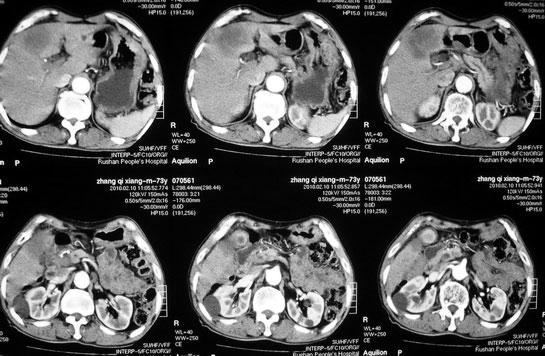

肝胆管细胞癌

患者AFP正常,无肝病病史。CA199 1000ng/ml,CEA偏高。血象WBC正常,N偏高。

这个病人是有病理的,做了肝活检,初八出结果。

化脓性胆囊炎累及肝脏;胆管细胞癌;肝转移瘤

活检病理

:是

胆管细胞癌

。

这个病人开始就是主要鉴别的肝脓肿和胆管细胞癌。可是增强后环征也不明显,占位内造影也非常不明显。这种情况怎么判断?谢谢大家。

病灶强化幅度较轻,低密度坏死区内见无定形高密度影,是其特点。